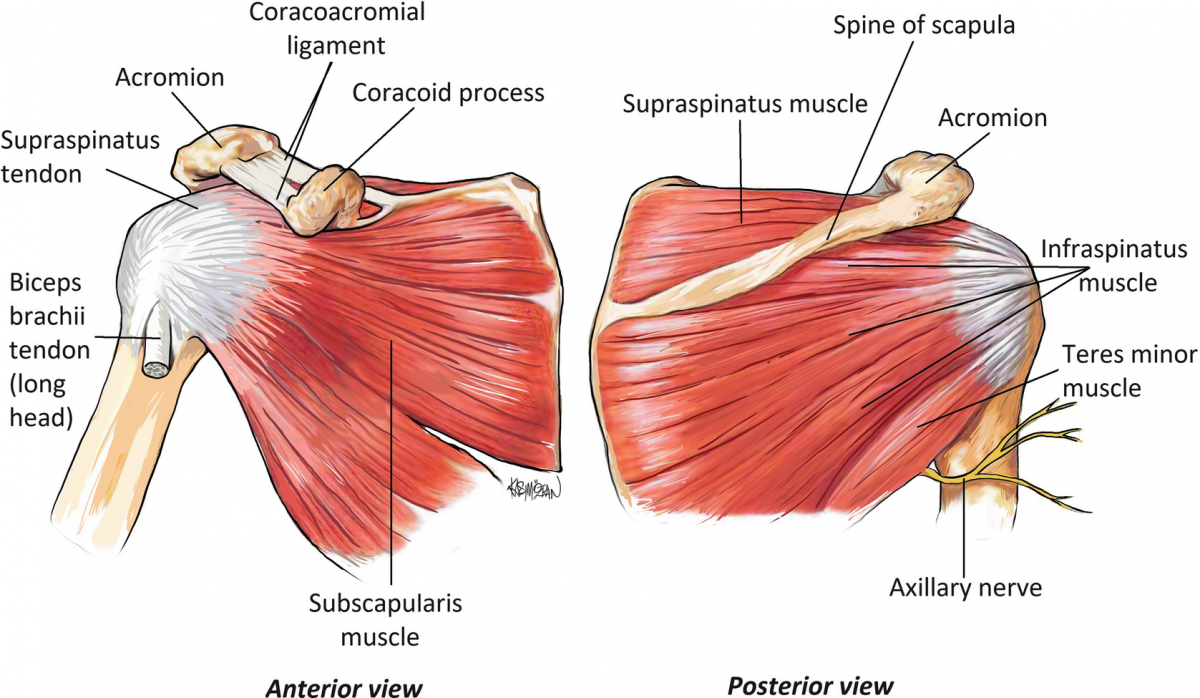

Фотографии поддельтовидной мышцы плечевого сустава